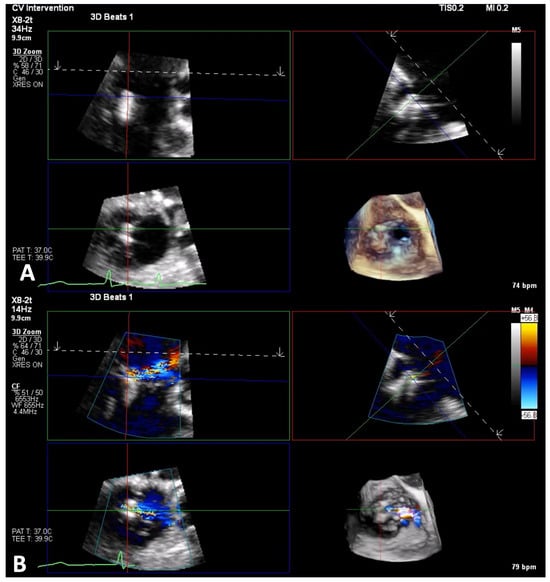

6.1. TEE-Guided Tricuspid TEER